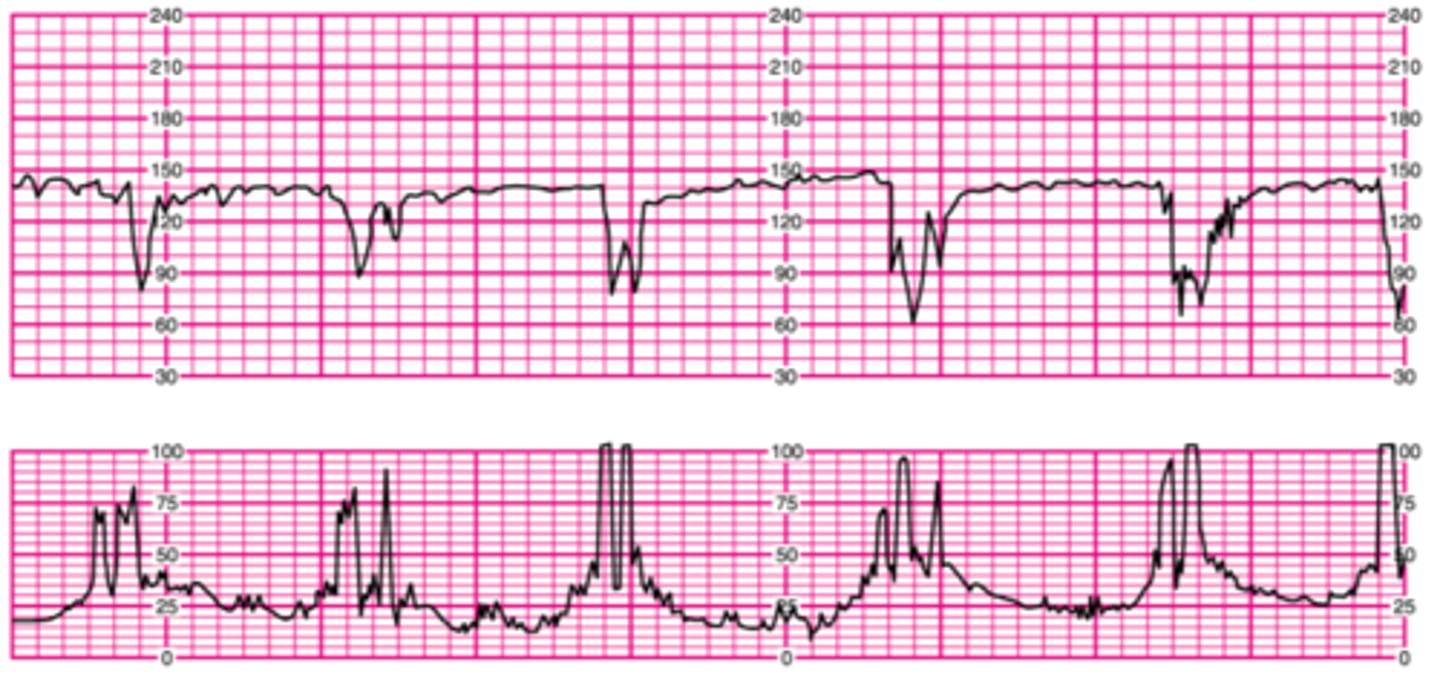

Variable deceleration

Abrupt deceleration; onset to nadir <30 seconds; complicated and uncomplicated

Uncomplicated decelerations

Type of variable deceleration; ≥15 bpm below baseline for ≥15 sec BUT <60 seconds

Cord compression

What is the main cause of uncomplicated variable decelerations?

True

True or false? Uncomplicated variable decelerations are normal as long as they are not repetitive

Complicated decelerations

A type of variable deceleration that lasts >60 secs AND decreases to 60bpm or less OR the heart rate deceleration is equal or greater than 60bpm below the baseline

Cause of complicated deceleration

Fetal depletion of reserves/hypoxemia related to significant cord compression